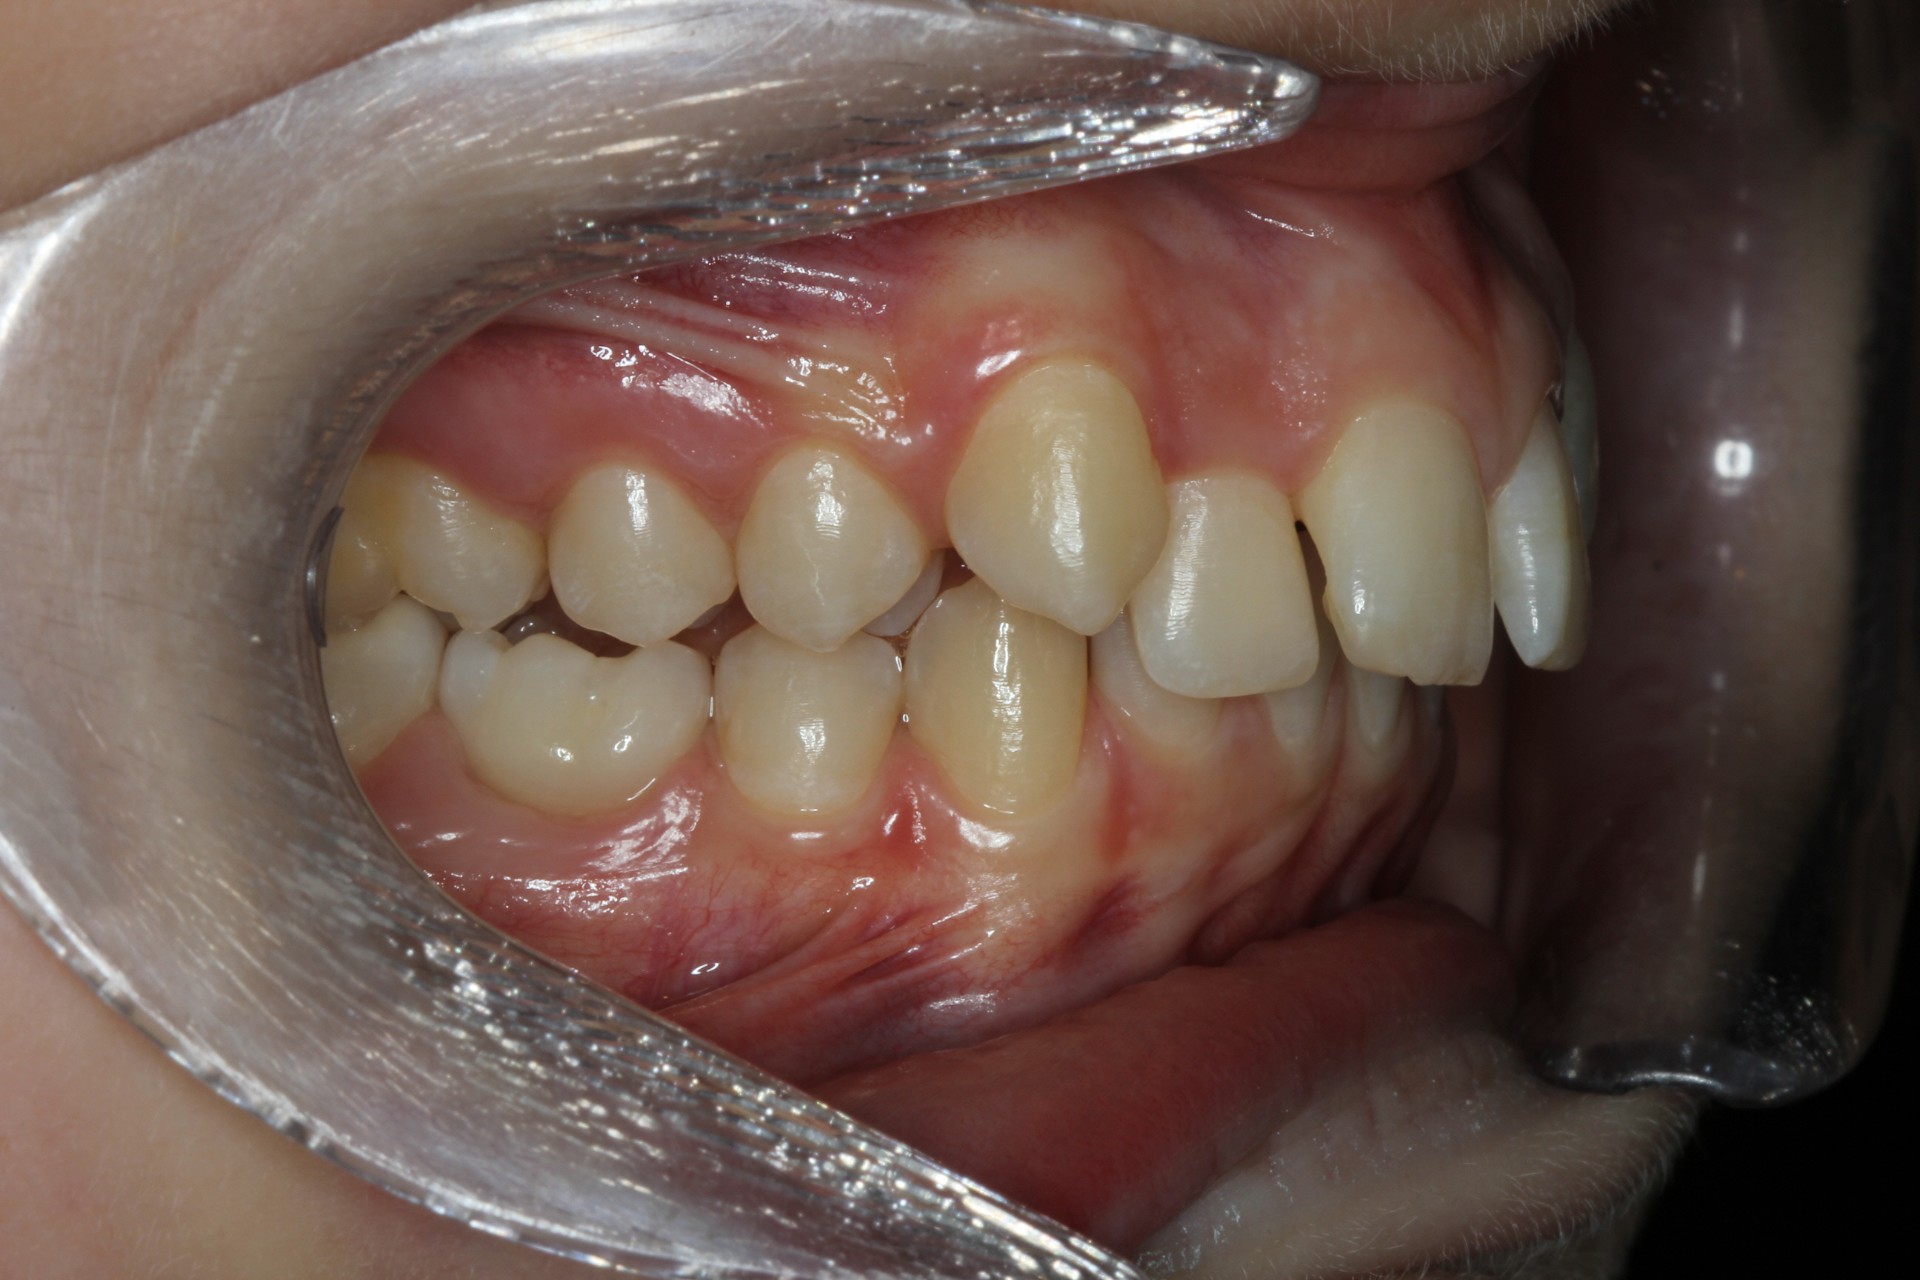

Protruding front teeth – Child case

Protruding front teeth and spacing – Child case

Protruding front teeth with midline diastema – Child case